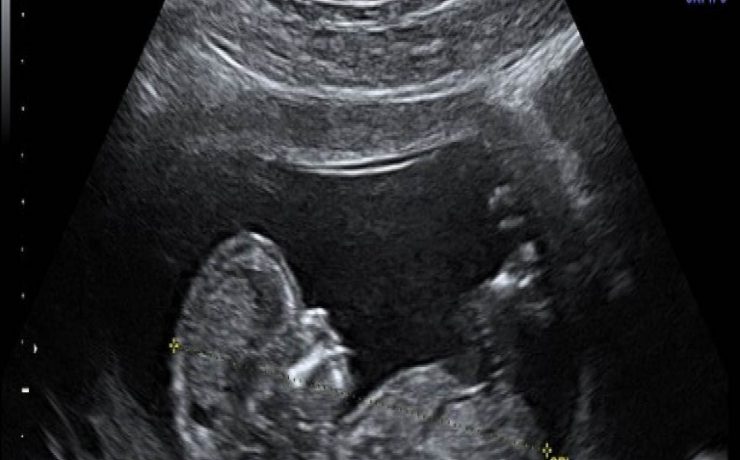

LA IMPORTANCIA DE LA ECOGRAFIA A LAS 11+0 A 13+6 SEMANAS DE EMBARAZO

Al principio, el ultrasonido en el primer trimestre se empezó a utilizar para medir la longitud cráneo-caudal del feto y estimar la edad gestacional, pero actualmente, además de eso, se evalúan varios detalles que permiten hacer una evaluación completa para identificar factores de riesgo que compliquen la gestación. Los objetivos